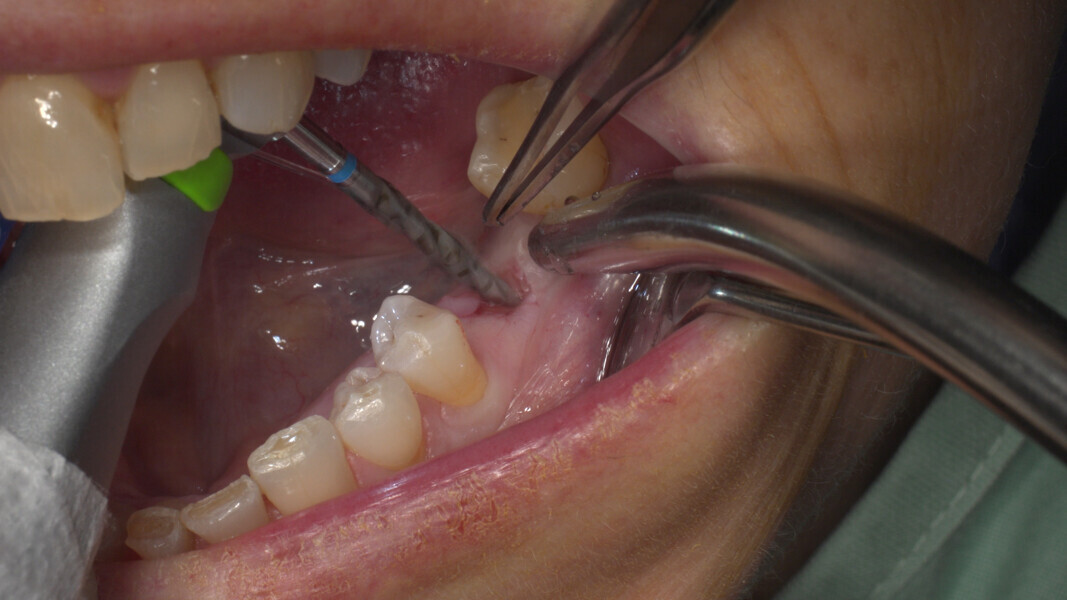

Conventional and immediate loading with final n!ce screw-retained crowns